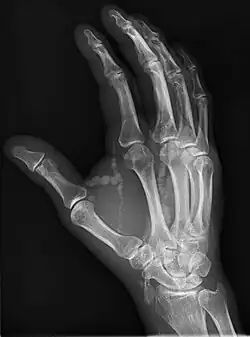

Oblique hand radiograph showing tumoral calcinosis

Oblique radiograph of the right hand demonstrating soft tissue calcification, characteristic of dialysis related metastatic calcification.